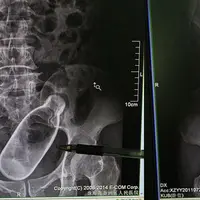

BeautyPutus Asa Karena Sembelit, Pria Ini Memasukkan Botol ke Tubuhnya

Akibat tindakan desperated pria yang tak mau disebutkan namanya ini, botol tersebut malah masuk dan terkunci di dalam anus. Adanya botol tersebut diketahui setelah dia melakukan pemeriksaan dengan sinar-X di salah satu rumah sakit di Cina.